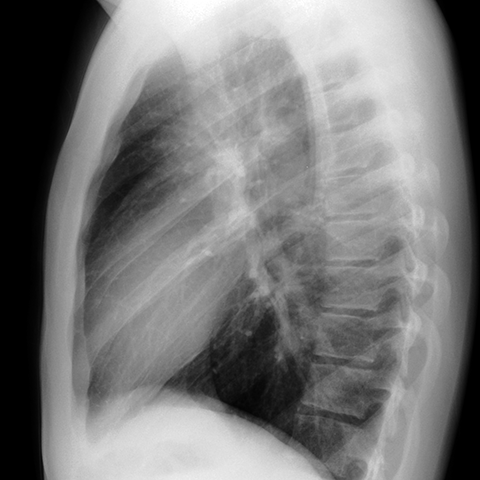

Normal Heart (Lateral CXR) [2 of 6]